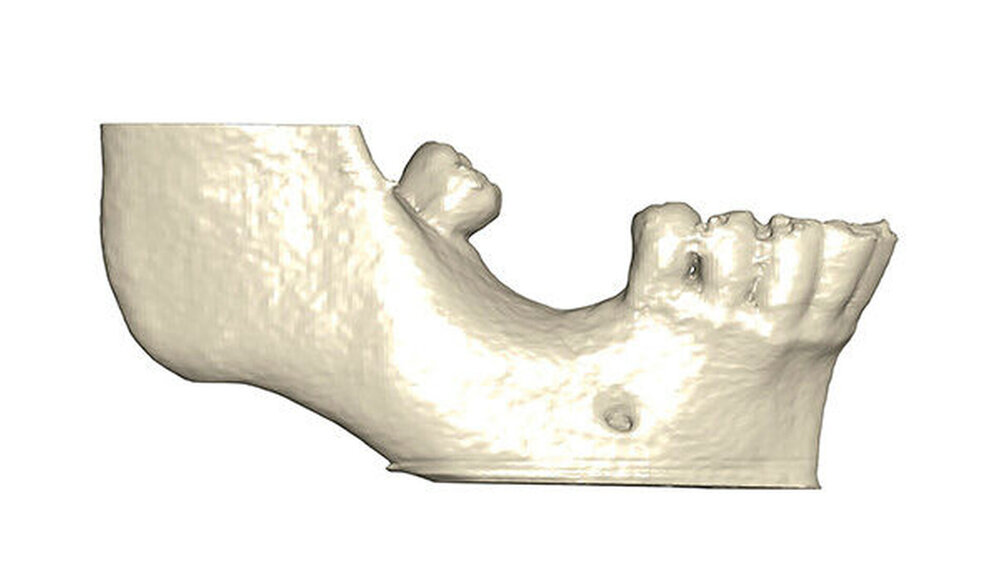

Ein 29-jähriger Patient stellte sich mit einer massiven Alveolarkammatrophie im rechten Unterkiefer in unserer Praxis vor. Diese lag in langen Jahren der Zahnlosigkeit begründet. Eine Beckenkammaugmentation kam für den Patienten nicht in Betracht. Dennoch wünschte er die Versorgung mit festsitzendem Zahnersatz. Nach ausführlicher Beratung entschied sich auch dieser Patient für eine Augmentation mit einem patientenindividualisierten allogenen CAD/CAM-gefertigten Knochenblock. Die DICOM-Daten des Unterkiefer-DVTs wurde an die Firma Zimmer gesendet, und es erfolgten wie im oben beschriebenen Fall eine virtuelle Planung und das virtuelle Design des allogenen Knochenblocks anhand der geplanten Implantatpositionen. Nach der üblichen Kontrolle und Freigabe des Chirurgen erfolgte die eigentliche Fertigung und Übersendung des Knochenblocks in die Praxis. Die Augmentation erfolgte auch in diesem Fall in Vollnarkose unter antibiotischer Abschirmung perioperativ mit Ampicillin. Die Schnittführung im Unterkiefer unterscheidet sich von der Sockelschnittführung im Oberkiefer aufgrund der Anatomie (N. mentalis). Auch bei diesem Patienten wurde eine tief im Vestibulum liegende bogenförmige Inzi‧sion durchgeführt, jedoch ohne die vertikalen Entlastungen. Nach streng subperiostaler Präparation erfolgte die Darstellung des N. mentalis. Die Vorbereitung des Spenderbetts sowie die Wässerung, Einpassung und Befestigung des allogenen Knochenblocks gestalteten sich wie im Fallbeispiel 1. Die Heilzeit des Knochenblocks dauerte ebenfalls sechs Monate. Zwei Implantate (Straumann) wurden nach krestaler Schnittführung in Lokalanästhesie eingebracht und heilten subgingival binnen drei Monaten ein. Aufgrund des massiven Volumenzuwachses war auch ebenfalls eine Vestibulumplastik im Zuge der Implantatfreilegung notwendig. Das Prozedere verlief ebenfalls wie im Fallbeispiel 1. Das freiliegende Gewebe wurde mit einer Kollagenmatrix abgedeckt. Dadurch konnte die Breite der befestigten Gingiva deutlich verbreitert werden.